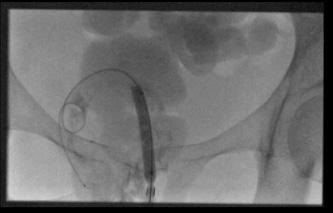

经臀-需要在骶棘韧带以上入路(高位经臀穿刺) High Transgluteal Drainage

高位经臀穿刺,需要在知情同意书上专门强调出血和针道疼痛的副作用较通常高

扫描架倾斜,扫描安全的进针途径 ![]() 经阴道(Transvaginal) 经会阴和经直肠穿刺通常也被成为经内腔(transendocavitory)穿刺引流。经阴道对盆腔脓肿进行手术引流是一种较成熟的方法,具有确定的益处,但大多数情况下,积液都使阴道壁移位,使这条通路的应用受到限制。可以在超声引导下进行引流,这样可以准确地将针头或导管放入积液内,这个积液的位置可以毗邻阴道穹窿,但没有使之变形。